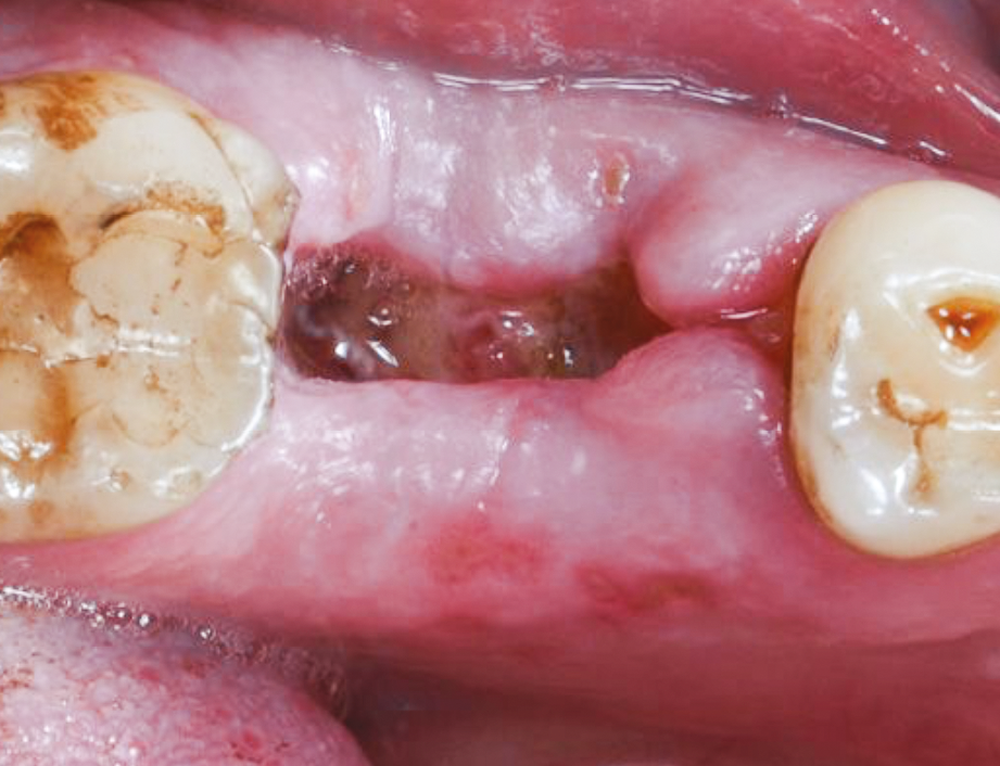

La douleur, principal motif de consultation postopératoire non programmé, doit toujours être vue comme un signe d’alerte. Il est donc essentiel, chez un patient qui est algique en postopératoire, d’exclure tout processus pathologique sous-jacent [2].

La réaction inflammatoire aiguë est un phénomène nécessaire à la cicatrisation, et c’est ce mécanisme qui va le plus souvent être responsable de la douleur postopératoire.

La douleur doit être évaluée (fig. 1) pour permettre la mise en place du traitement pharmacologique adapté (tabl. I). Ce traitement devra ensuite être réévalué et, le cas échéant, réadapté en fonction de son efficacité. Plusieurs molécules peuvent ainsi être associées pour exploiter leurs actions additives ou synergique ; on parle alors d’analgésie multimodale. Par exemple, un AINS est plus efficace quand il est associé au paracétamol. À noter, la grande prudence à adopter vis-à-vis de l’automédication des patients par AINS quand la présence d’un phénomène infectieux sous-jacent n’a pas été exclue.